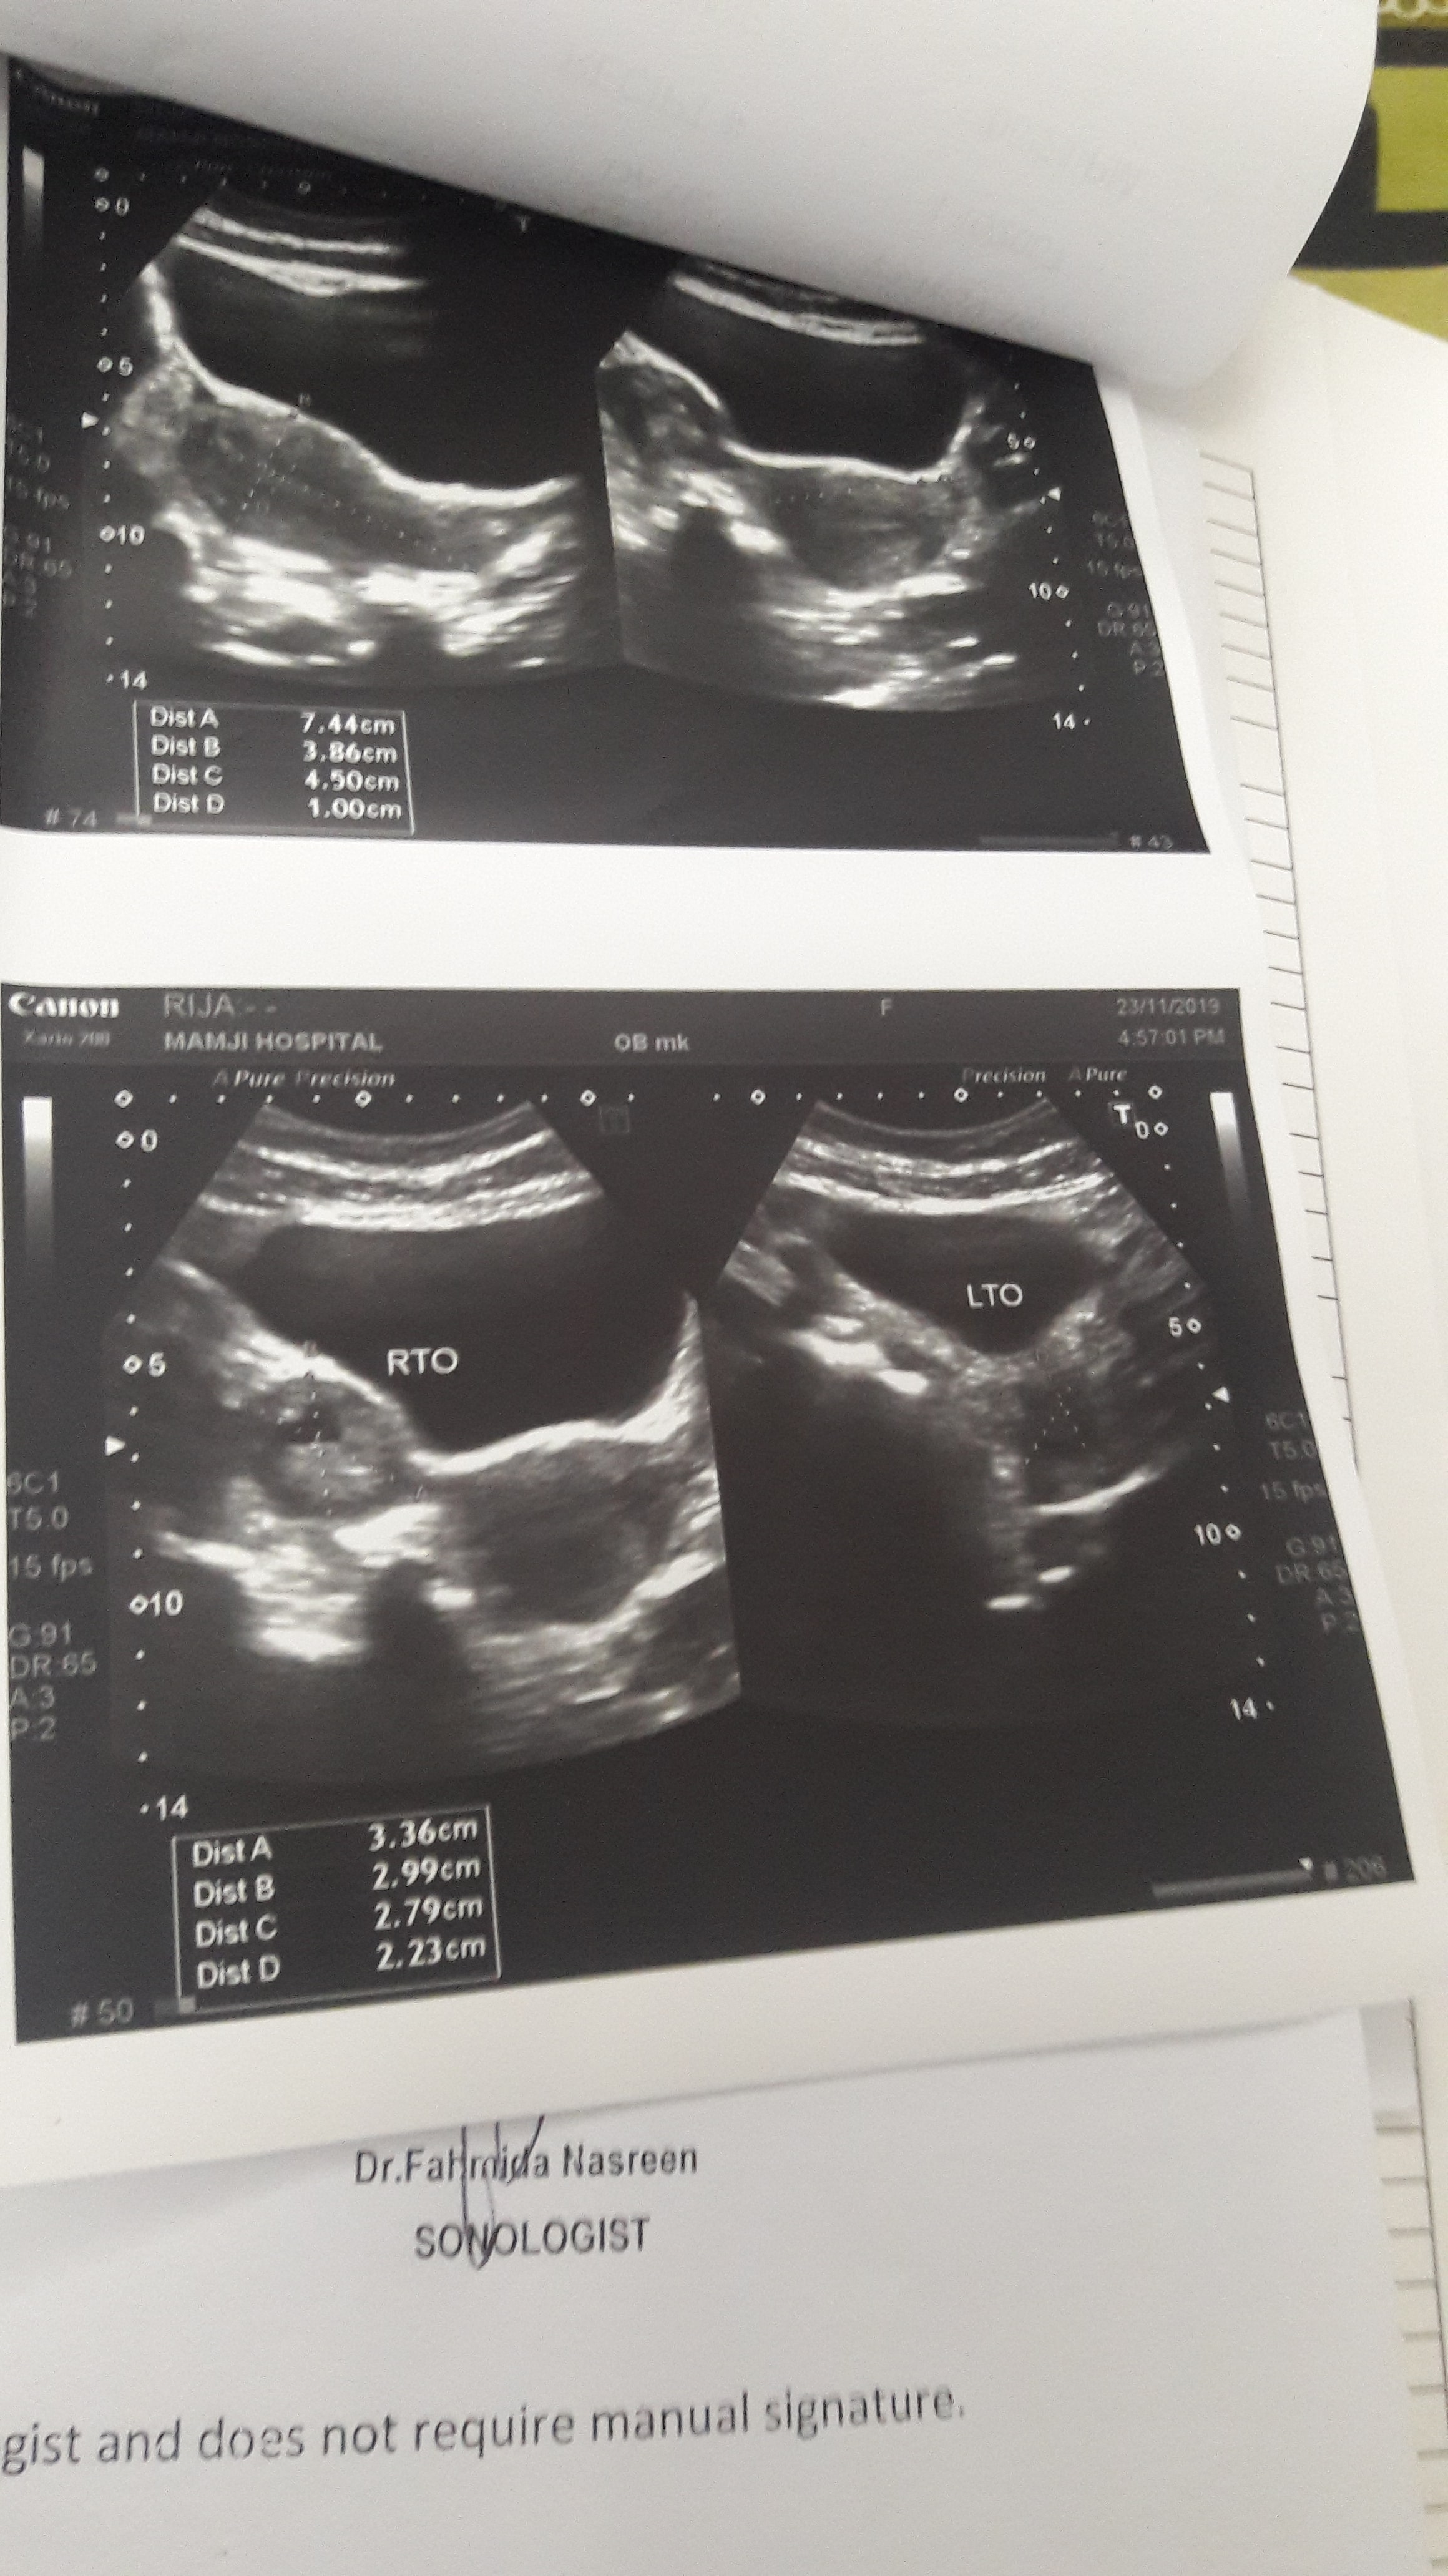

Mra abortion hua ha 1week baad bleeding kum hui ha ab ultra sound hua ha kindly mjhy ye reports dkh kr batadein abhi bhi baki ha?

Salam ur ultrasound appears fine . Take folic acid , iron and calcium . Thanks